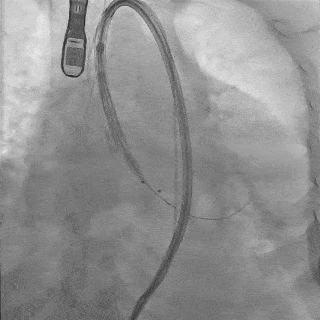

瓣膜稳定释放至全展开

造影观察:瓣膜位置可,形态佳